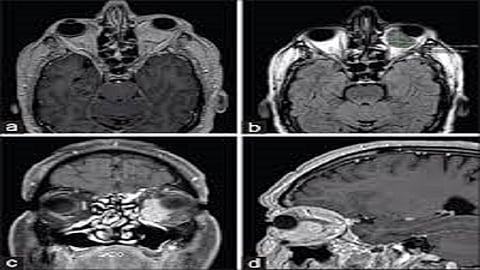

रुग्णालयात केलेल्या प्राथमिक तपासणीत तिला वाचायला येत नसल्याचे, तसेच उजव्या डोळ्याने एखादा चेहराही ओळखू येत नसल्याचे आढळून आले. श्रुतीची ‘एमआरआय’ तपासणी करण्यात आली. त्यामध्ये ‘इन्फिल्ट्रेटिंग एन्हान्सिंग सॉफ्ट टिश्शू मास लेशन’ असल्याचे दिसून आले. ‘सीटी गाईडेड बायोप्सी’ आणि ‘इम्युनोहिस्टो केमिस्ट्री’ या चाचण्याही करण्यात आल्या. त्यातून श्रुतीच्या आजाराचे निदान निश्चित झाले. तिला ‘रोसाई डॉर्फमन’ हा आजार (आयएचसी: S-100, CD-68 Expressed) झाला होता. हा आजार असलेल्या रुग्णांमध्ये ‘लिम्फाडेनोपथी’ वाढलेली आढळते (ही लिम्फ नोड्सची एक स्थिती आहे, यामध्ये हे नोड्स विचित्र पद्धतीने वाढतात). तसेच ताप, न्यूट्रोफिलिया, ल्युकोसिटॉसिस (पांढऱ्या रक्तपेशी वाढणे), ‘इएसआर’ मध्ये वाढ आणि ‘पॉलिक्लोनल गॅमोपॅथी’ ही लक्षणे आढळतात. हा अतिशय दुर्मिळ स्परुपाचा आजार असून 1969 पासून आतापर्यंत जगात या आजाराचे 1000 पेक्षाही कमी रुग्ण आढळून आलेले आहेत.